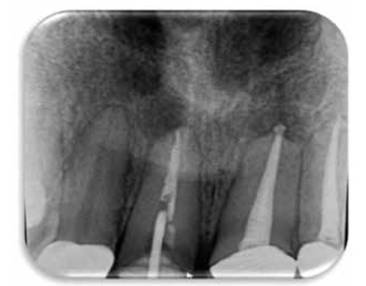

Se procede a remover la férula, corona y desobturar la pieza para colocar un alambre y poder realizar un muñón más estable para efectuar la extrusión ortodóntica. (Figuras 8A y 8B)

Figura 8A: Colocación temporal de alambre de ortodoncia de 0.9 mm de grosor, dentro del conducto y confección de muñón.

Figura 8B: Nótese la estabilidad del periodonto.